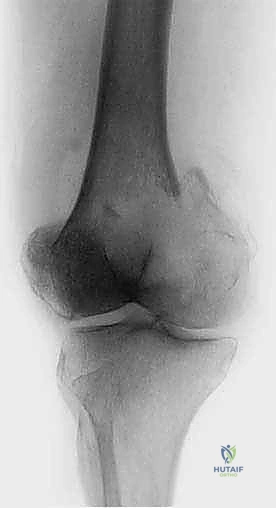

2. استئصال الورم وتغيير المفاصل (Tumor Resection & Endoprosthetic Arthroplasty)

في الحالات التي يدمر فيها الورم المفصل بالكامل (مثل مفصل الورك أو الركبة)، يقوم الدكتور هطيف باستئصال الجزء المصاب من العظم والورم معاً، واستبداله بمفصل صناعي خاص بالأورام (Megaprosthesis). بفضل خبرته الواسعة في تغيير المفاصل، يستطيع المريض المشي في اليوم التالي للعملية!

| عظم الفخذ (القسم العلوي) | كسر عنق الفخذ، العجز عن المشي. | استبدال مفصل الورك بمفصل صناعي (Arthroplasty). |